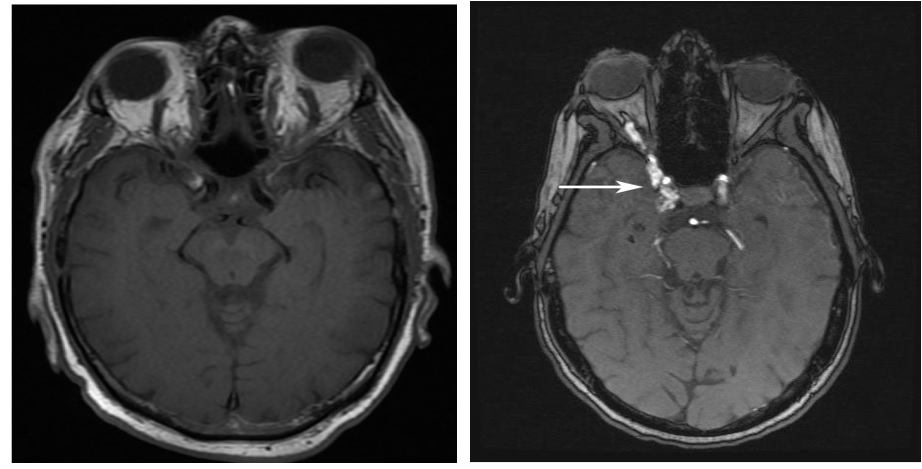

Dò xoang hang